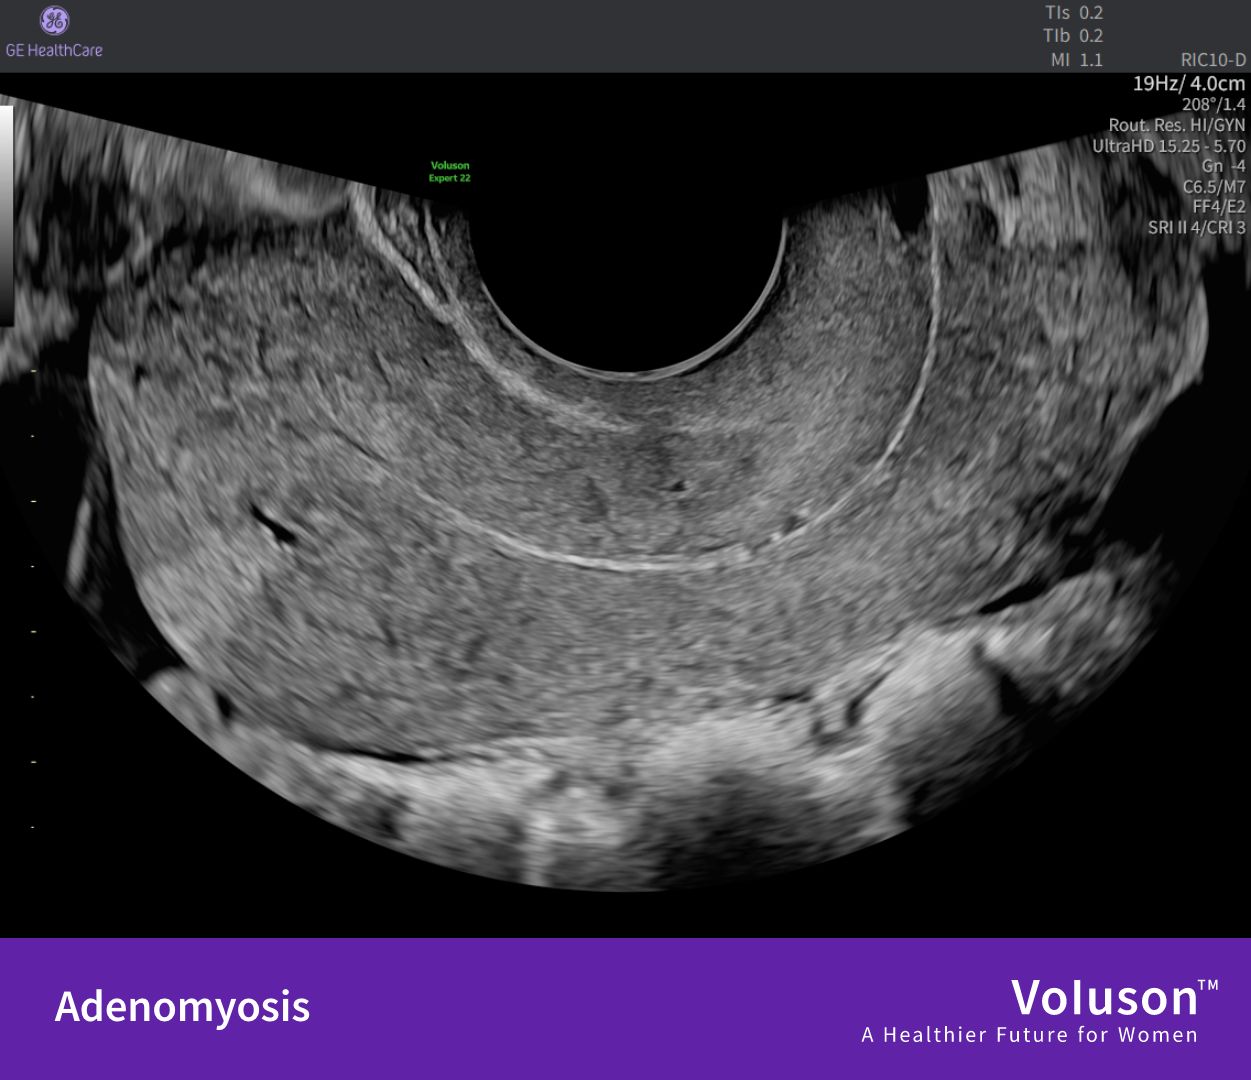

“Similar – but not the same: Adenomyosis vs endometriosis

Adenomyosis and endometriosis share many features – overlapping symptoms, similar impact on patients’ lives, and frequent underdiagnosis.

However, they are two distinct conditions that require different approaches to care.

For adenomyosis, experts propose a practical classification grounded in ultrasound findings.

Swipe through our slides of how adenomyosis and endometriosis might appear in clinical practice!